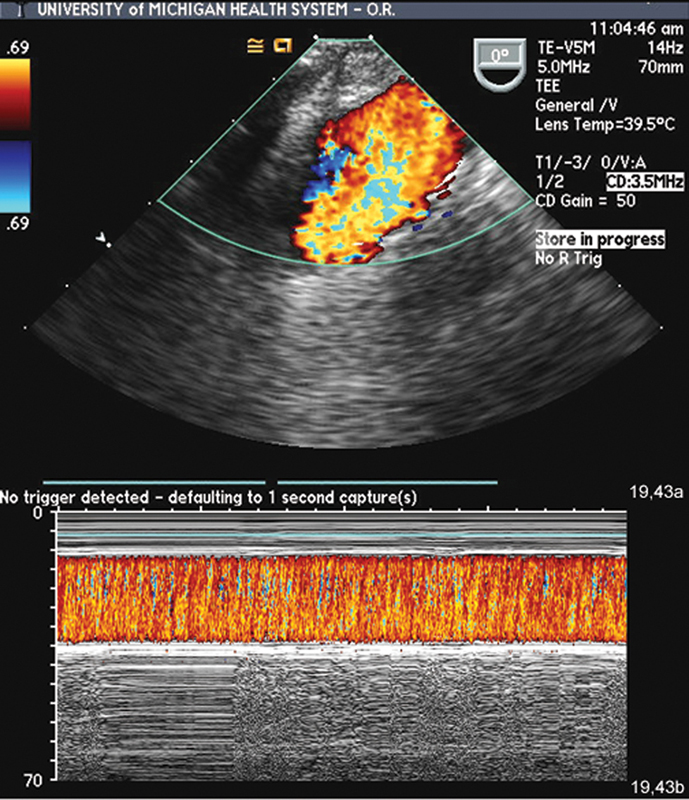

فحوصات تشخيصية لبعض امراض القلب والشرايين التاجية